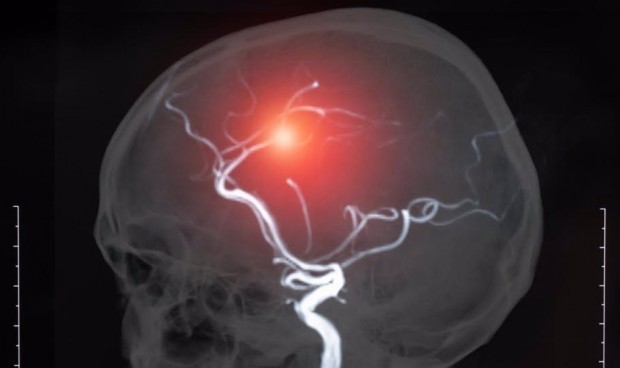

Pruebas de imagen para diagnosticar pacientes con ictus

La Sociedad Española de Radiología Médica (SERAM) estima que aproximadamente la mitad de las peticiones urgentes de pruebas de imagen están relacionadas directa o indirectamente con pruebas asociadas a pacientes con ictus y en el contexto del día mundial del ictus reivindica la labor fundamental del radiólogo.

El radiólogo cumple un papel fundamental en el diagnóstico y tratamiento del ictus, ya que en el momento actual es el profesional especializado en la interpretación de las pruebas de imagen diagnósticas que incluyen la tomografía computarizada y la resonancia magnética. Además, “el radiólogo cumple un papel fundamental también en el proceso de diagnótico y tratamiento del ictus relacionada directamente con la optimización, la gestión y el desarrollo de las pruebas de imagen. La presencia de un profesional de la Radiología garantiza que en todo momento el paciente se encuentre en un entorno seguro, muchas veces con pruebas relacionadas con radiaciones ionizantes, y que las pruebas se realicen e interpreten de forma adecuada evitando el desperdicio de recursos”, apunta Murias.

El trabajo multidisciplinar con el resto de los servicios del hospital, principalmente con las unidades de ictus y los Servicios de Urgencias y Neurología, así como la relación con los técnicos de imagen y con los profesionales de la enfermería, permite optimizar los tiempos de diagnóstico y de tratamiento. “Recordemos que uno de los factores más importantes para conseguir un buen prono funcional de los pacientes es el diagnóstico rápido mediante pruebas de imagen y en este entorno una adecuada gestión de los recursos es básico para no introducir retrasos en la cadena del código ictus” señala Murias.